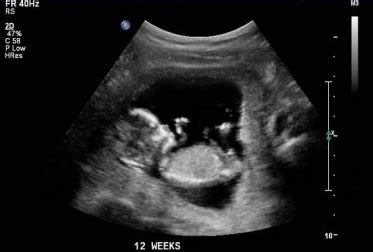

Již máte za sebou 7 týdnů těhotenství, nejkrásnějšího zázraku na světě, zrození nového života. Osmý týden těhotenství znamená konec druhého kalendářního měsíce. Vašemu miminku rostou a vyvíjejí se v tomto období ruce, nohy, nos, pusa, uši, ale i mozek. Velké změny se dějí také s vaším tělem. Zdvojnásobí se objem krve, aby bylo Vaše miminko dostatečně vyživováno. Těhotenství mění metabolismus a také krevní oběh ženy. Tvoří se střeva, srdce rychle bije, formují se také ušní lalůčky, oční víčka, ústa a nos. Koncem 12. týdne dosahuje embryo délky okolo sedmi centimetrů a hmotnosti přibližně dvacet gramů. Zárodek roste rychleji a zrychluje se také vývoj jeho orgánů. Horní končetiny rostou rychleji než dolní.

Ultrazvukové měření je dnes jedním z nejčastěji používaných diagnostických nástrojů při sledování zdraví a vývoje plodu v děloze. Tento postup v medicíně umožňuje lékařům a porodním asistentkám získat přesné informace o velikosti a vývoji dítěte na základě konkrétních parametrů, jako jsou délka stehenní kosti, obvod hlavy a břicha nebo celková odhadovaná váha plodu. Do 20. týdne těhotenství se plod měří od temene ke kostrči. Od 20. týdne těhotenství se plod měří na základě výpočtového vzorce, kde zadáváme parametry, jako jsou průměr hlavičky, obvod hlavičky, obvod bříška a délka stehenní kosti.